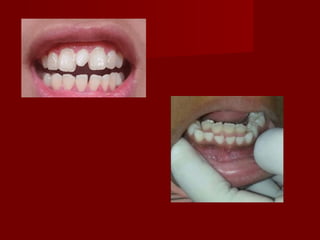

 Aetiology of Dental crossbiteAetiology of Dental crossbite

– due to lack of space for permanent teethdue to lack of space for permanent teeth

CausesCauses

– Permanent tooth buds from lingual to thePermanent tooth buds from lingual to the

primary teeth, a shortage of space may causeprimary teeth, a shortage of space may cause

the permanent maxillary incisor teeth to remainthe permanent maxillary incisor teeth to remain

lingual to the line of the arch and erupt intolingual to the line of the arch and erupt into

crossbitecrossbite

 Supernumerary teethSupernumerary teeth

 retained deciduous teethretained deciduous teeth

 tooth size discrepancytooth size discrepancy

 Abnormal eruptive pathAbnormal eruptive path

( ectopic eruption )( ectopic eruption )